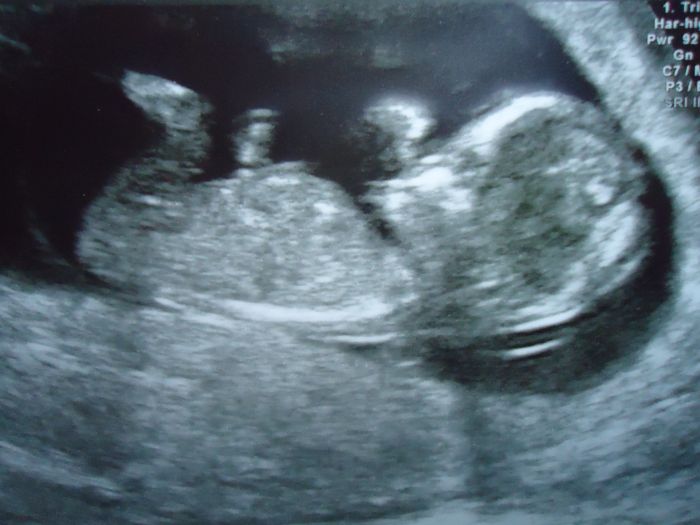

Jinak jsem predevcirem dostala prukazku, protoze jsme sli na screening, kde ji chteli. Byla jsem uplne na nervy a modlila se, at tam je, hybe se, tluce srdicko a vyrostlo. Ze zacatku dobre, mame krasnou fotku, pak ho to stouchani utz rozlitilo a bylo k nezastaveni. Pekne skotacilo a je dokonce o 6 dni vetsi. Musela jsem se smat, jak ho doktorka honila a nemohla presne zmerit to, co potrebovala. Bylo to krasne...

Kaci, jsem ve 13tt. Trochu jsem bojovala, jak to dostat do pc, ale tady je to nase krasne miminko.

Pomněnko,moc krásný mimísek. Je to stejně zázrak,jak z toho vyroste človíček.

Pomnenko moc krásná fotečka ;) dneska jsem mněla takový nepříjemný zážitek.Jedné zákaznice jsme zamítli reklamaci běžeckých bot a ona se naštvala a začala mi tam nadávat že jsem tlustá a nevím nic o běhání atd. mněla jsem chut ji něco říct ale kousla jsem se do jazyka...njn mám 68kg,ale co to je za chování....